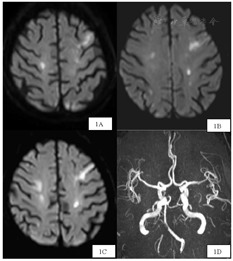

超声心动图:双房增大(左房48 mm,右房46 mm×55 mm),射血分数60%,主动脉瓣、二尖瓣、三尖瓣少量反流,轻度肺动脉高压;颈动脉超声:双侧颈动脉斑块形成,右侧椎动脉起始段狭窄(狭窄率50%~69%);下肢动脉超声:双下肢动脉斑块形成、左侧胫后动脉闭塞、左侧腓动脉近闭塞;下肢静脉超声:左侧胫后静脉血栓形成;腹部超声:肝脏实性占位性质待定;脾大;胆囊壁增厚;右肾囊肿。腹部CT:肝S6段占位性病变;考虑恶性病变;胆囊结石;慢胆囊炎;慢性胰腺炎伴假性囊肿形成;双肾囊肿(图2)。